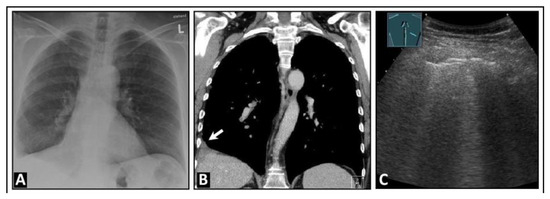

3. Underlying Pathology in Artifacts

6. Interstitial Lung Disease

7. Other Pathologic Situations